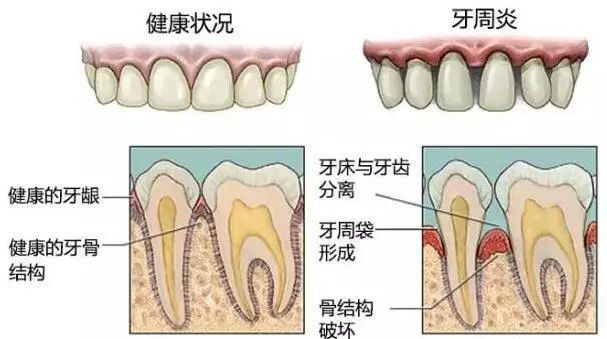

正常健康的牙龈状况,在牙与牙之间填充着满满的牙龈。从剖面图来看,你会看见其实还是有一些小的缝隙存在,但是被牙龈和牙周组织支撑得很好。

牙周炎患者的牙龈状况,牙与牙之间有大大的缝隙,牙龈红肿退缩,暴露出了牙根。从剖面图看,明显的牙龈和牙周组织的萎缩,骨头的吸收也非常明显。